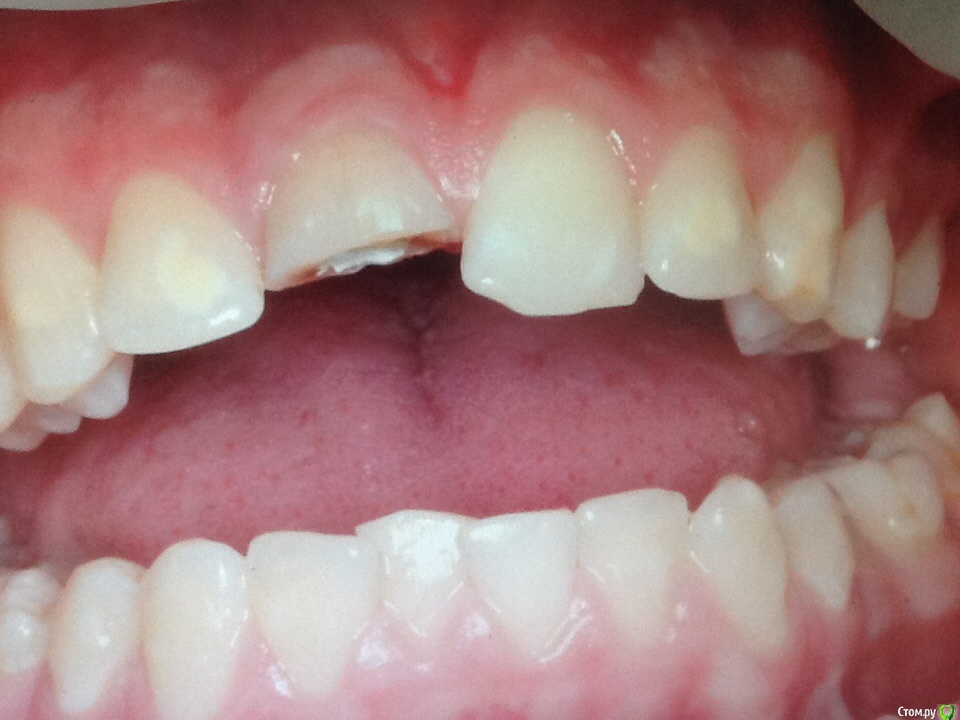

Л Ю С Я Опубликовано 8 октября, 2015 Поделиться Опубликовано 8 октября, 2015 Пациент получил травму в 6 летнем возрасте со вскрытием пульпы. 1.1 Явился в теч 6 часов. Со слов детского стоматолога( коллеги), сделала ампутацию пульпы, закрыли сицем. Ходил год, наблюдался, потом родители забили на это. Появились через 8 лет с просьбой сделать коронку емах, подростка беспокоил внешний вид)))) детский стоматолог начала работу, звонит мне, мол там камень, все ничего не могу сделать. Ссылка на комментарий